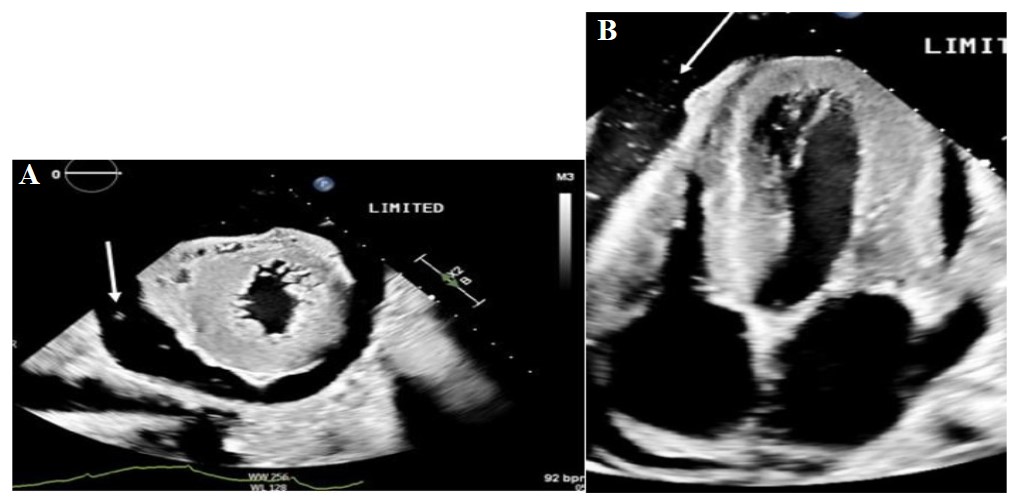

Figures 1:(A) Two-dimensional transthoracic echocardiogram, parasternal short axis view demonstrating bright echodensities within the pericardial fluid consistent with bubbles. (B) Two-dimensional transthoracic echocardiogram, apical four chamber demonstrating bubbles in the pericardial space.

A 56-year-old female with a history of atypical Chronic Myeloid Leukemia (CML) and right upper lobe pulmonary adenocarcinoma presented to the outpatient clinic with shortness of breath and fatigue. She had undergone right robotic thoracoscopy, right upper lobectomy, and complete thoracic lymphadenectomy two months earlier. One month later, a chest tube had been placed due to findings of an empyema/malignant effusion. Laboratory studies completed at the clinic demonstrated significant hyperleukocytosis and she was referred for admission. In the emergency room, she was afebrile and normotensive, blood pressure 122/86 mmHg, with heart rate of 95/min and respiratory rate 25-30/min, O2 saturation was 95% on room air. Physical exam revealed a cachectic, ill-appearing female with decreased breath sounds in both lung bases and bilateral lower extremity edema. Laboratory results included white blood cell count 82,000, platelet count 997,000 and hemoglobin 8.4 g/ dL. Other significant blood tests included uric acid 10.3 mg/ dL, phosphorus 6.6 mg/dL and LDH 1,054. SARS-COV2 was not detected. Chest X-ray showed post-surgical changes compatible with right upper lobectomy, a small right apical pneumothorax and bibasilar opacities. A non-contrast chest CT scan performed that day demonstrated a moderate right and a small left pleural effusion, with compressive atelectasis and loculated fluid and gas within the right upper lobectomy cavity. An abdominal CT showed scattered foci of gas within the small bowel wall consistent with Pneumatosis Intestinalis (PI). Hepatosplenomegaly, splenic infarcts, and ascites were also noted (Figure 1). A Transthoracic Echocardiogram (TTE) done the following day showed normal left ventricular function with an ejection fraction of 60-65% and a large pericardial effusion. Small, bright echodensities were seen in the pericardial fluid, consistent with microbubbles. There was no evidence of tamponade.

Symptoms may include shortness of breath and sharp chest pain [2]. On examination, the characteristic auscultatory sound referred to as bruit de moulin, which has been attributed to the interaction of air and fluid in the pericardium, may be heard. Electrocardiogram may show evidence of pericarditis, nonspecific ST changes, and low voltages [4]. The “halo sign”, an area of radiolucency surrounding the heart shadow, can be seen on plain radiography and is diagnostic. Associated pneumomediastinum, pneumothorax, or pneumoperitoneum may also be seen radiographically. Subcutaneous emphysema has been described in some cases associated with dental surgery and central venous catheters. CT scans offer further delineation of pneumopericardium and other air collections. TTE findings include the “air gap sign” which refers to changing of the cardiac shape in a cyclic fashion due to the air in the pericardial sac and the “swirling bubbles sign” manifested as small echogenic spots due to the presence of microbubbles at the air-fluid interfaces generated by the movement of the heart [10] as seen in our case. Notably, the halo sign, seen in most cases, was absent in our case and diagnosis was made by echocardiography. An asymptomatic, hemodynamically stable pneumopericardium does not require specific treatment and may resolve spontaneously. However, monitoring for conversion to tension physiology with signs of tamponade is essential. If a tension pneumopericardium is present, immediate decompression is required as mortality rates as high as 50% have been shown [1,2].